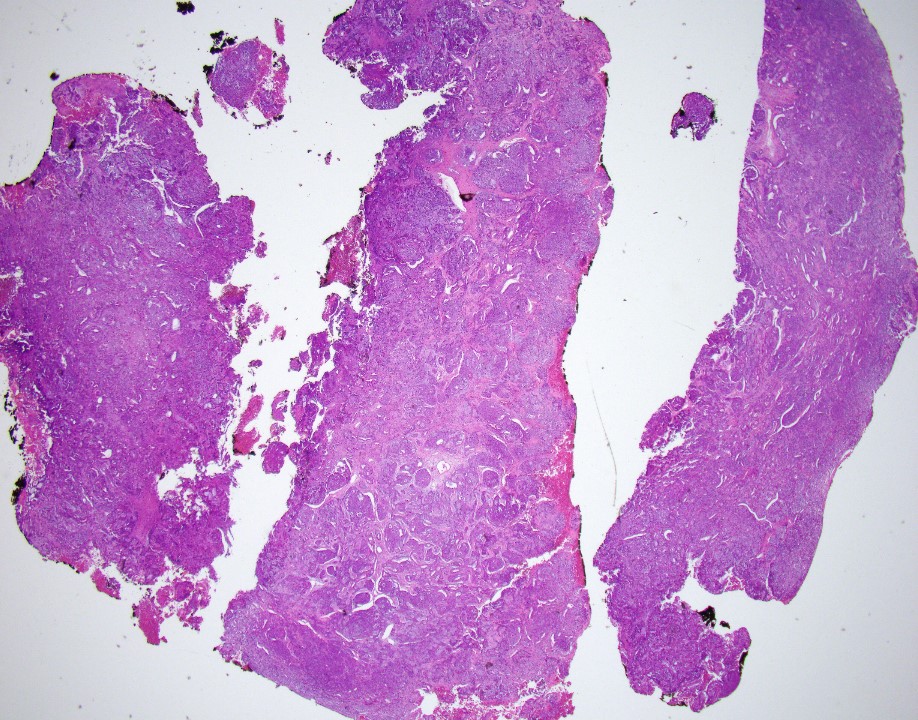

75 years old female. MR image shows a 5.2 x 4.4 x 4.0 cm perianal mass. This is left perirectal mass biopsy:

Answer: A. Adenoid cystic carcinoma

The neoplasm reveals mixed epithelial and myoepithelial components, without significant cytologic atypia, embedded in a chondromyxoid stroma. The epithelial component shows strong cytoplasmic positivity with cytokeratin (AE1/AE3), while the myoepithelial component is positive for S100 protein and p63 (with all appropriate controls). Salivary Duct Tumor Gene Fusion Analysis detected MYB-NFIB gene fusion, which supports this is an adenoid cystic carcinoma.